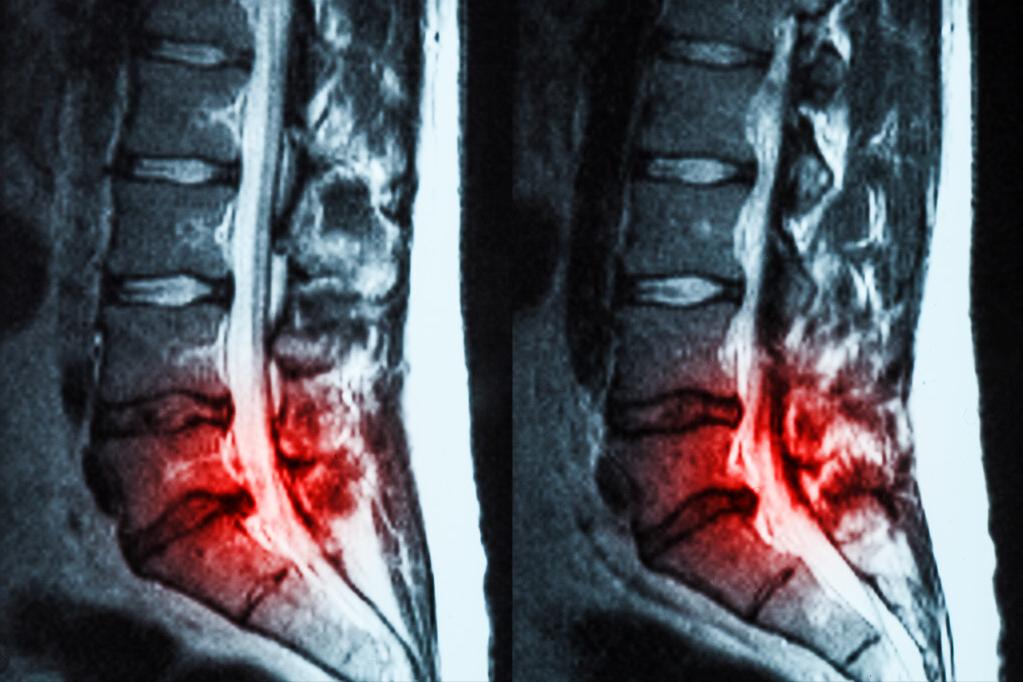

神经功能障碍:顾医生曾收治一名患者,老年男性,因为腰椎间盘的突出入院,入院的时候他就是有排尿困难的表现,那么给他检查了一下,发现有会阴部的感觉障碍,而且他在腰痛之前就有排尿不畅的表现,现在已经每次小便只能排出几滴,症状很严重。最终手术的时候尿管也插不进去,只能进行腹壁的膀胱造瘘。

其实这就是属于腰椎间盘突出造成的马尾神经受压,马尾神经支配排尿相关的肌肉造成排尿不畅,同时他还合并有前列腺肥大,即使解除了神经压迫,也还是有排尿困难,这就是比较复杂的情况。

总结:如果你经常有腰痛、腿麻、腿痛,再加上有排尿困难的话,要尽快去医院就诊,因为神经压迫时间越长,恢复得越慢也越困难。